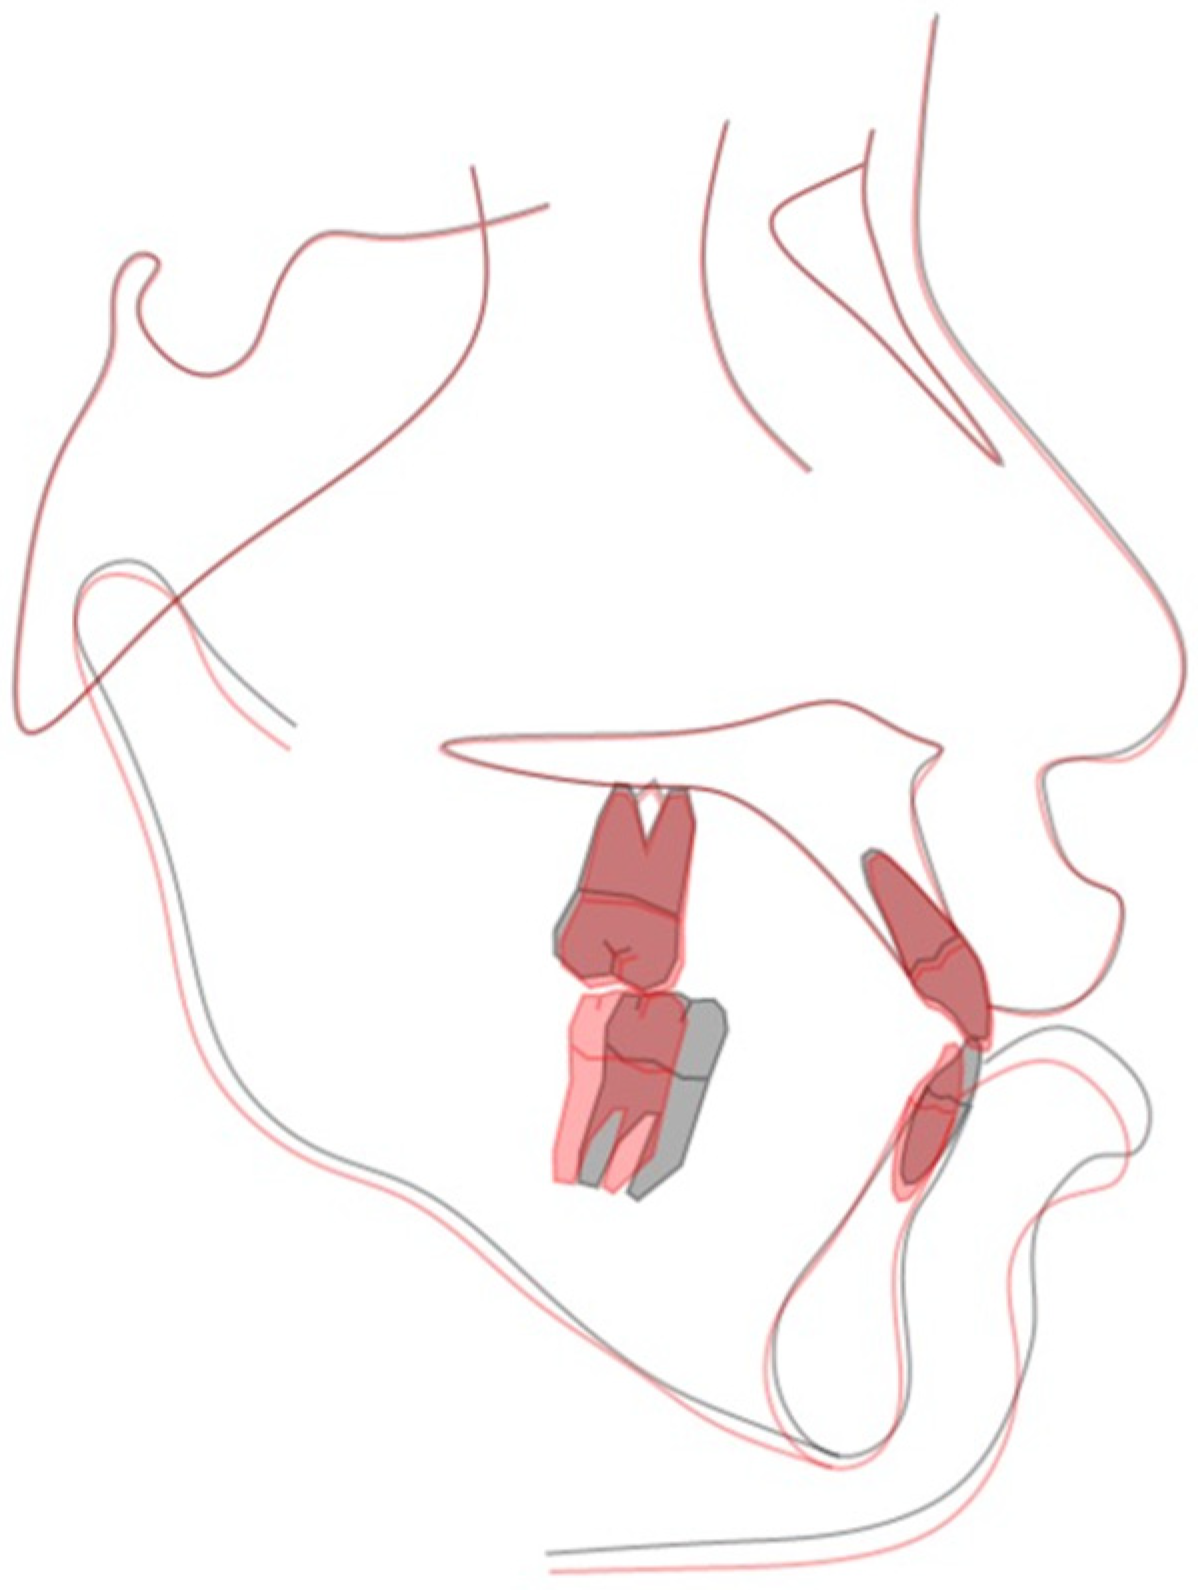

2.5. Treatment Results

| Norms | 1st Phase Pretreatment | 1st Phase Post-Treatment | 2nd Phase Pretreatment | 2nd Phase Post-Treatment | |

| SNA (°) | 81.5 ± 3.5 | 81.6 | 81.7 | 81.2 | 81.5 |

| SNB (°) | 77.7 ± 3.2 | 79.4 | 79.9 | 79.3 | 78.8 |

| ANB (°) | 4.0 ± 1.8 | 2.2 | 1.8 | 1.9 | 2.7 |

| SN-MP (°) | 33.0 ± 1.8 | 39.7 | 43.0 | 45.0 | 45.4 |

| Dental analysis | |||||

| U1-NA (mm) | 3.9 ± 2.1 | 2.7 | 4.8 | 4.9 | 4.7 |

| U1-NA (°) | 24.0 ± 4.0 | 23.5 | 26.4 | 27.9 | 25.6 |

| U1-SN (°) | 108.2 ± 5.4 | 107.1 | 109.4 | 109.0 | 107.1 |

| L1-NB (mm) | 6.6 ± 2.8 | 6.1 | 7.1 | 6.8 | 5.8 |

| L1-NB (°) | 25.0 ± 5.0 | 25.7 | 27.8 | 28.7 | 22.0 |

| L1-MP (°) | 96.8 ± 6.4 | 78.1 | 82.3 | 84.3 | 77.8 |

| U1-L1 (°) | 124.2 ± 8.0 | 128.9 | 124.1 | 121.5 | 129.7 |

| Facial analysis | |||||

| E-line/UL (mm) | −1.1 ± 2.2 | 0.4 | 0.8 | −0.4 | −0.4 |

| E-line/LL (mm) | 0.5 ± 2.5 | 5.1 | 6.0 | 6.1 | 5.2 |